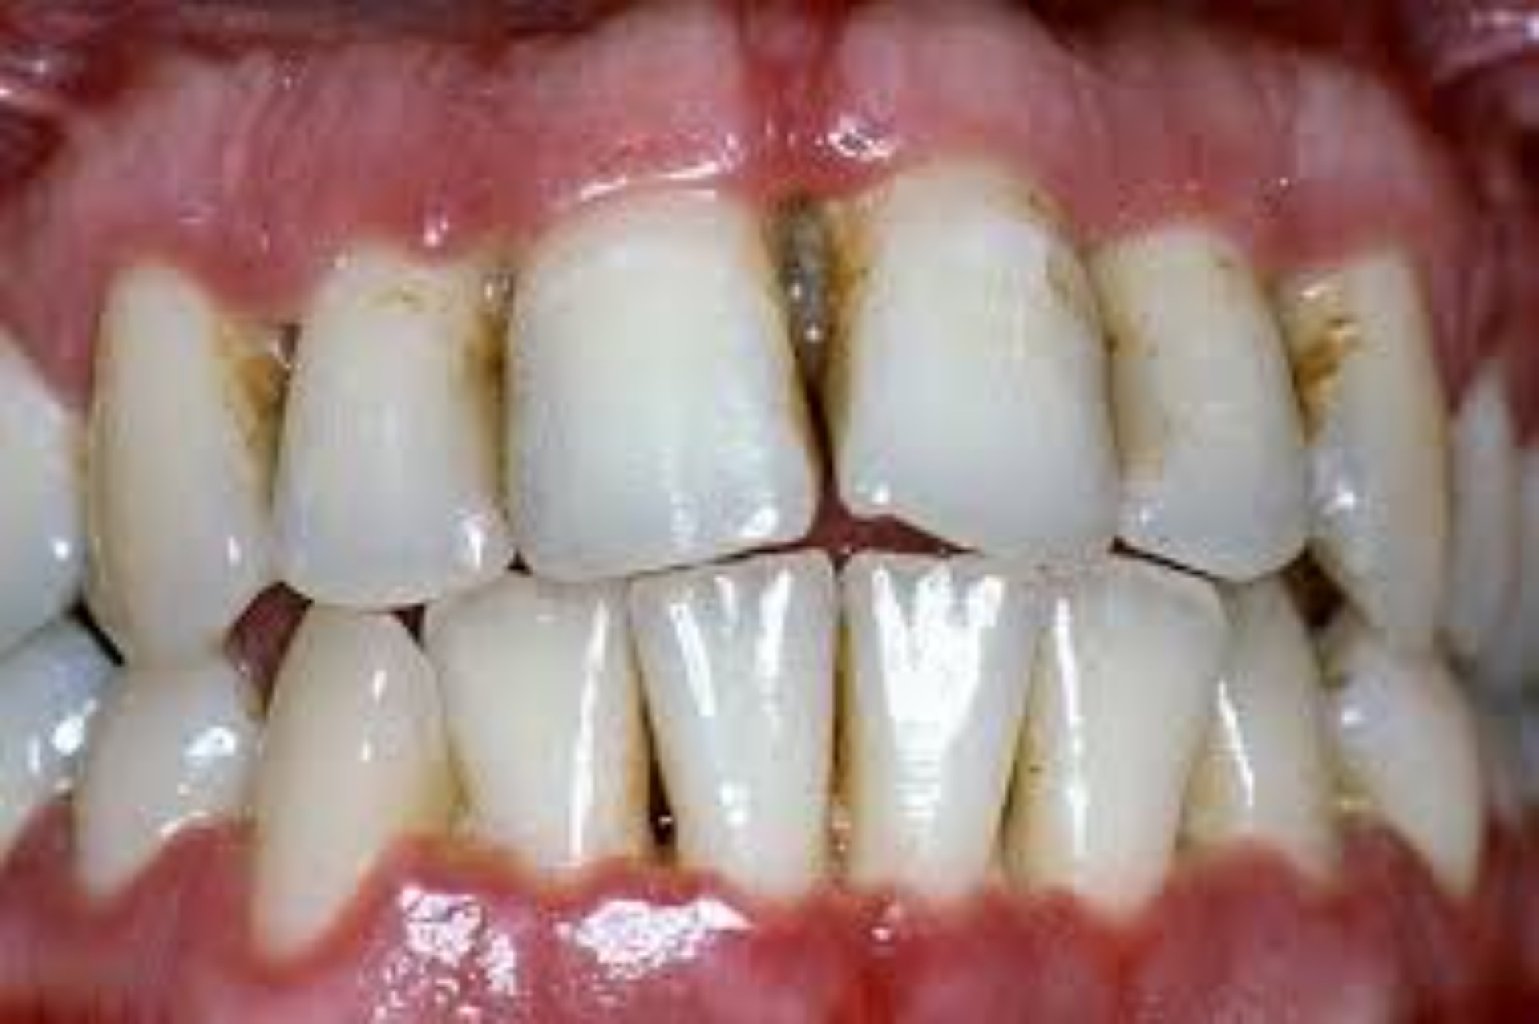

Estetik Diş əti Səviyyələndirilməsi Prosedurları: Gingivektomiya: Bu, artıq diş əti toxumasının ç ...